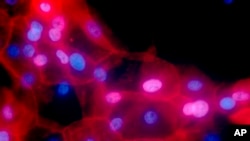

Hemoterapija, zračenje i operacija su standardne metode lečenja karcinoma. Ali, hemoterapija i zračenje zajedno sa malignim ubijaju i zdrave ćelije, a nuspojave su opšte poznate. Lečenje raka danas nastoji da bude preciznije i da terapije deluju samo na kancerogeno tkivo.

Drugi tretmani uključuju testiranje genetskog materijala od kojeg su napravljene ćelije raka I lek koji uništava samo te ćelije.

Svaki karcinom je jedinstven, baš kao i njegov DNK. Na osnovu toga se i utvrđuje koji je lek najdelotvorniji. Zdrave ćelije se ne uništavaju, a nuspojave se mogu ublažiti.